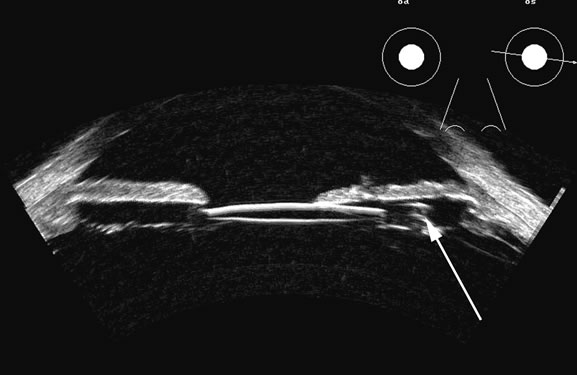

Fig. 17. This patient with a Molteno tube was treated for glaucoma. The top 50 MHz B-scan clearly shows the Molteno Tube (arrow). The bottom 10 MHz B-scan of the same patient demonstrates a choroidal detachment (large arrow) with associated posterior retinal detachment (small arrow). Choroidal elevations are typically convex, highly reflective surfaces with posterior limitation at the vortex vessels. Retina will always attach at the optic nerve. Choroidal elevations are often noted in several quadrants, as seen here.